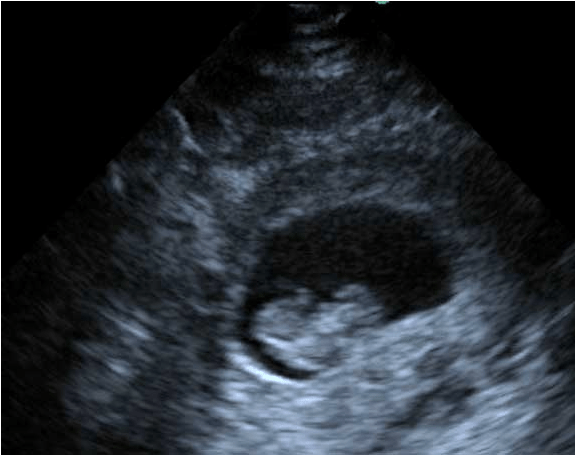

More recently, lung ultrasound has been explored for the assessment of a suspected PE. A recent systematic review and meta-analysis by Squizzato et al which included 10 studies and a total of 887 patients found lung ultrasound to have a mean sensitivity of 87% and a mean specificity of 82% for acute PE12. What they looked for in the lung was the presence of triangular, wedge or rounded hypoechoic, pleural based lesions. These lesions are thought to be due to embolic occlusions that resulted in either focal atelectasis with extravasation of blood or focal infarction of the lung parenchyma . However, they state in their publication that “Several methodological drawbacks of the primary studies limit any definite conclusion”.

Lung infarction:

Now back to our patient. She is a 46 year-old female with COPD that had right heart enlargement, which we learned above can be seen in COPD without the presence of a PE. You were unable to get a good subcostal view of the heart to measure the lateral wall, mostly because the patient did not tolerate being laid flat. You move on to the lungs and in the lower right thorax and there you find two hypoechoic, pleural based lesions. Heparin and a CT scan are ordered, and the CT scan shows a large clot located in the right main pulmonary artery.